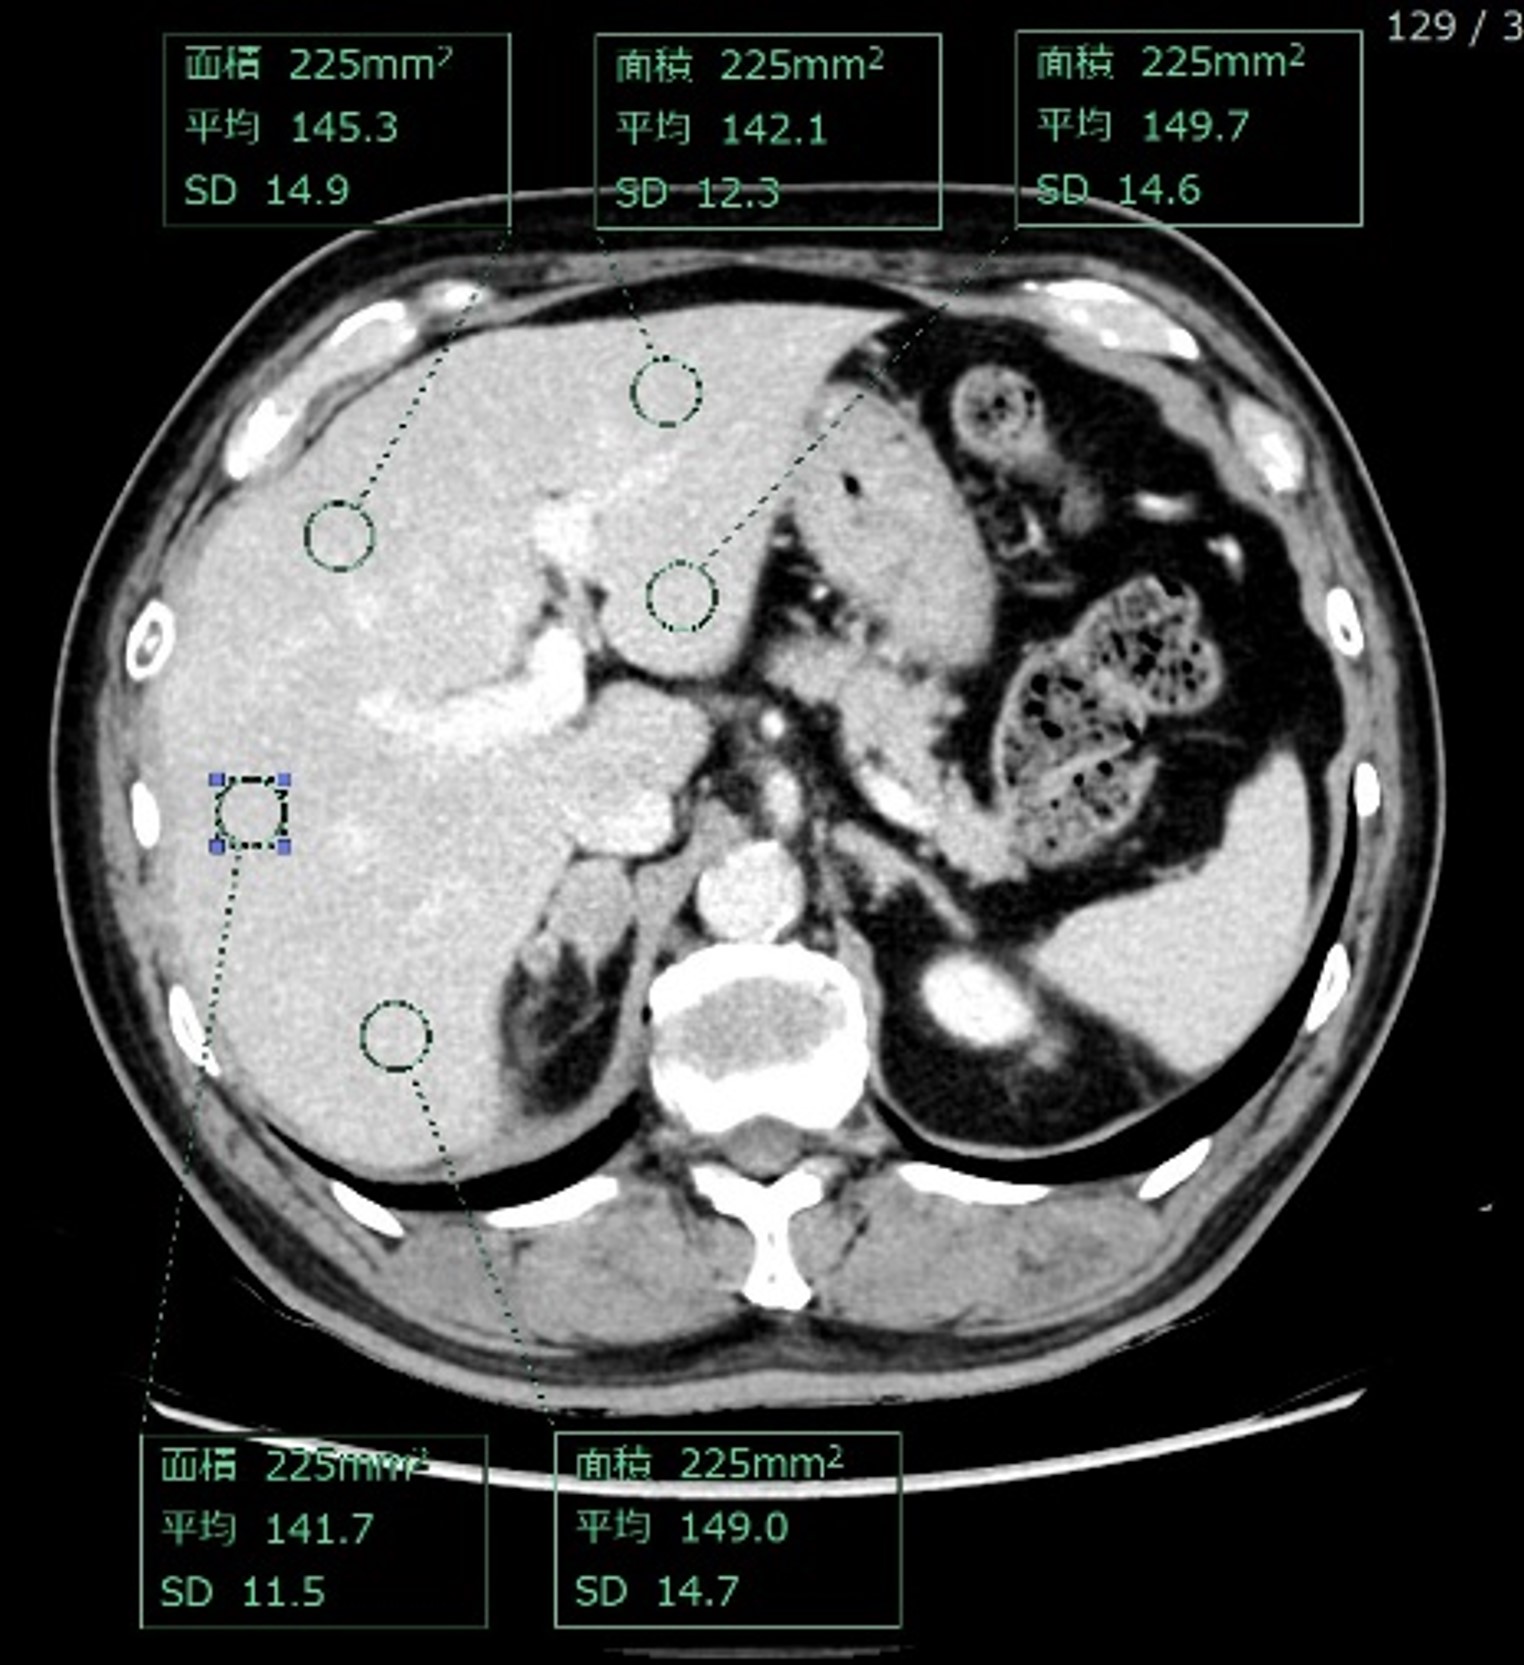

しかしEliteでは高出力のX線管球に加えディープラーニング再構成であるTrueFidelity DLにて画像再構成が可能であるため、低エネルギーのモノクロマティック画像であってもノイズを低減した画像を提供できている。図2の通り300 mgI/mL製剤 59 mL(0.9 mL/sec)で造影したにもかかわらず、肝臓のCT値は約145 HU、また画像SDは約13.6と診断能を損なわない画像を提供できた。なおこの画像は図1に示す通り、体重85kg、体重当たり ヨード使用量210mgI/kgであることを強調したい。

RevolutionApexElite_Uonuma203.jpg

図2 45 keV 2.5 mm Axial計測